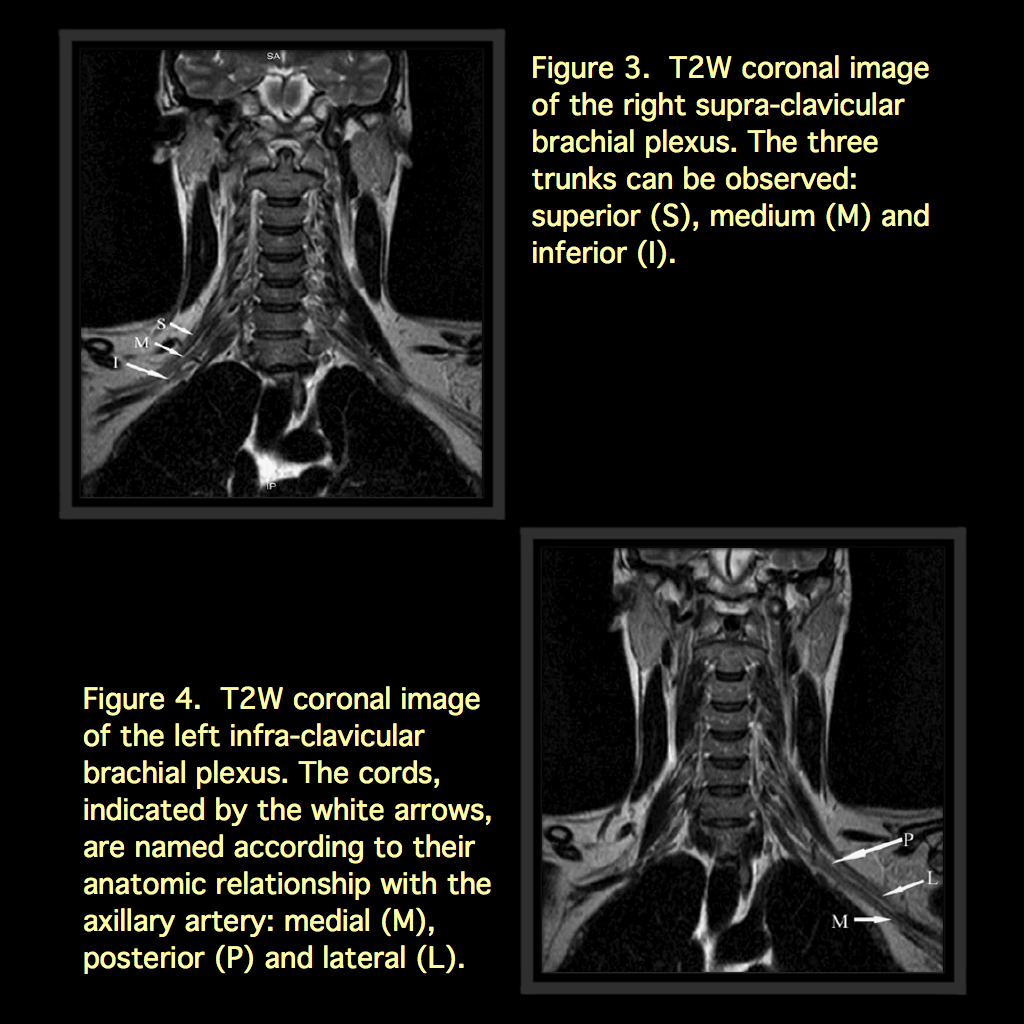

From www.ejradiology.com

MRI of the brachial plexus A pictorial review European Journal of What Is A Mri Brachial Plexus Mri of the brachial plexus provides detailed images to diagnose nerve injuries, tumors, and other abnormalities in the brachial plexus region. Mri of the brachial plexus is used to provide a causal diagnosis for brachial plexopathies. The brachial plexus is an intricate neural network that provides motor and somatosensory innervation of the arm, shoulder, and upper chest. This section of. What Is A Mri Brachial Plexus.